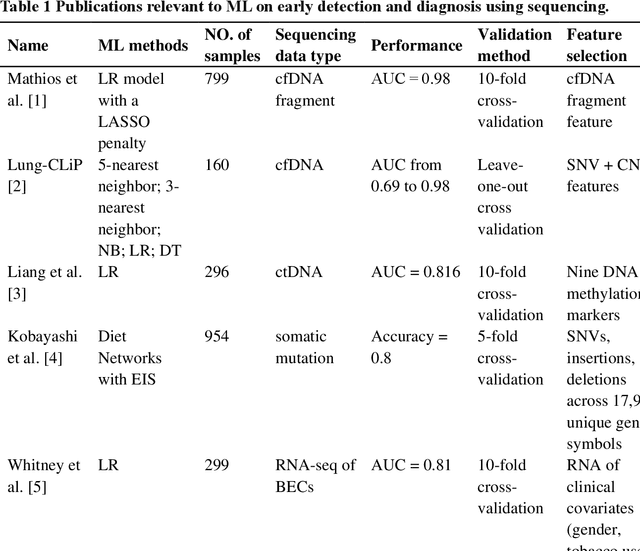

Machine Learning Applications in Diagnosis, Treatment and Prognosis of Lung Cancer

Mar 05, 2022

The recent development of imaging and sequencing technologies enables systematic advances in the clinical study of lung cancer. Meanwhile, the human mind is limited in effectively handling and fully utilizing the accumulation of such enormous amounts of data. Machine learning-based approaches play a critical role in integrating and analyzing these large and complex datasets, which have extensively characterized lung cancer through the use of different perspectives from these accrued data. In this article, we provide an overview of machine learning-based approaches that strengthen the varying aspects of lung cancer diagnosis and therapy, including early detection, auxiliary diagnosis, prognosis prediction and immunotherapy practice. Moreover, we highlight the challenges and opportunities for future applications of machine learning in lung cancer.